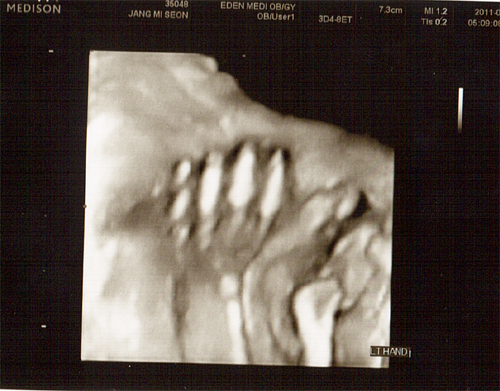

26주 4월 8일(금) 입체 초음파사진